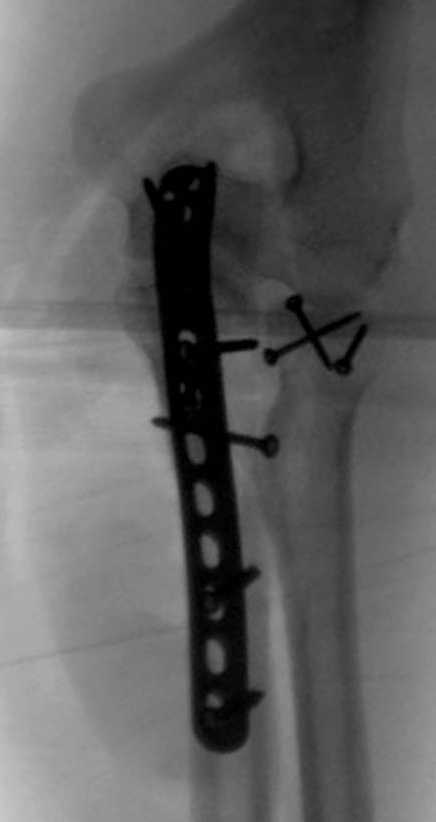

Здесь выставлены несколько случаев и варианты фиксации локтевого отростка, некоторые в комбинации с другими переломами.

1 вариант применен ACUMED локинг пластина

2 вариант

перелом локтевого отростка с переломом головки лучевой кости (использованы 2 мм шурупы)

3 вариант

перелом с capitelum humerus и проксимальной трети улна